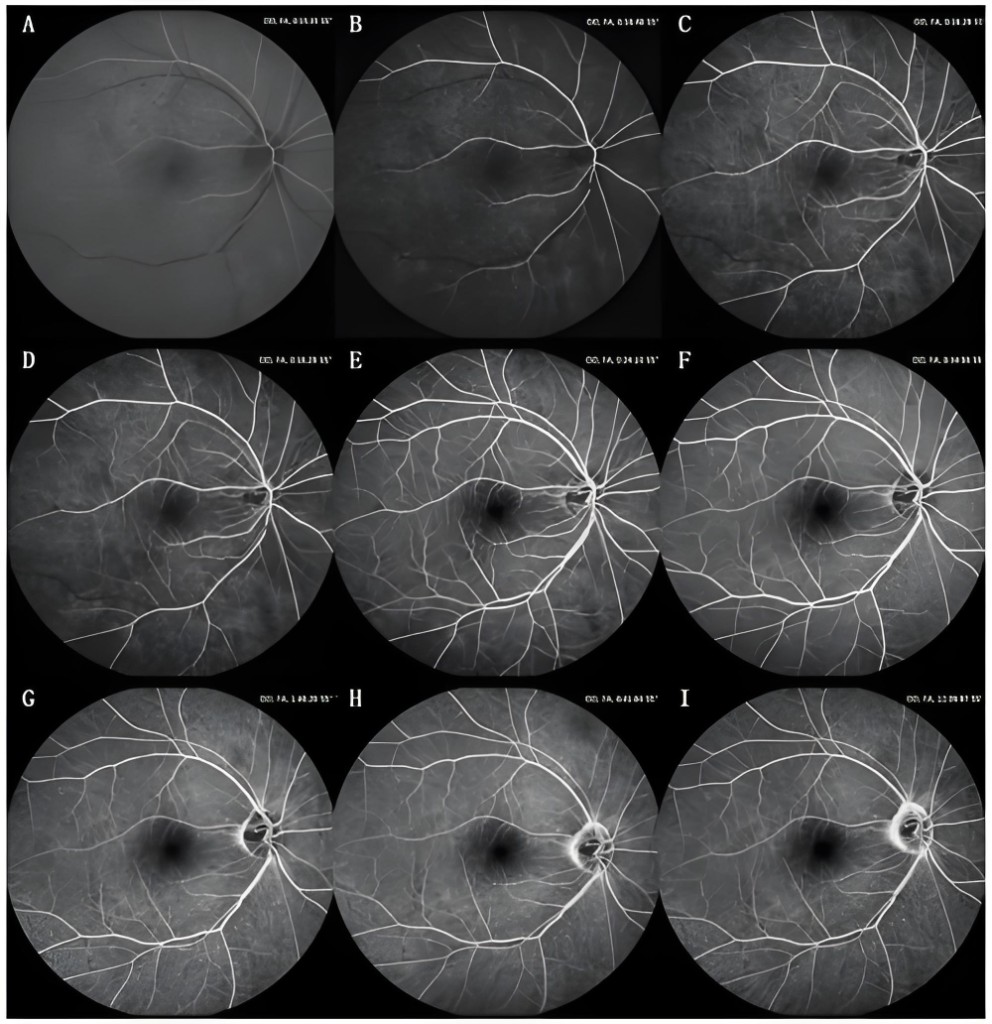

眼科超广角眼底彩色照相机

眼科 OCT 光学相干断层扫描成像仪

医学影像智能分析系统(眼科影像、肠道、宫颈)